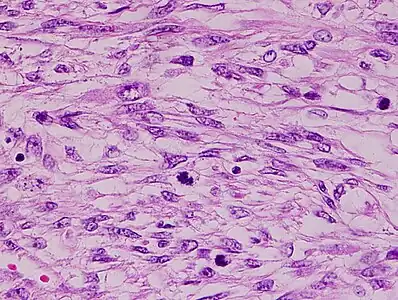

Myxoid leiomyosarcoma of bladder- 1) Abnormal mitosis 2) differentiated leiomyosarcoma 3) pools of hyaluronic acid -

Histopathology of leiomyosarcoma shows variable atypia, often with cytoplasmic vacuoles at both ends of nuclei, and frequent mitoses.[11]

Diagnosis of LMS is made by performing a soft-tissue biopsy and examining its histopathology.